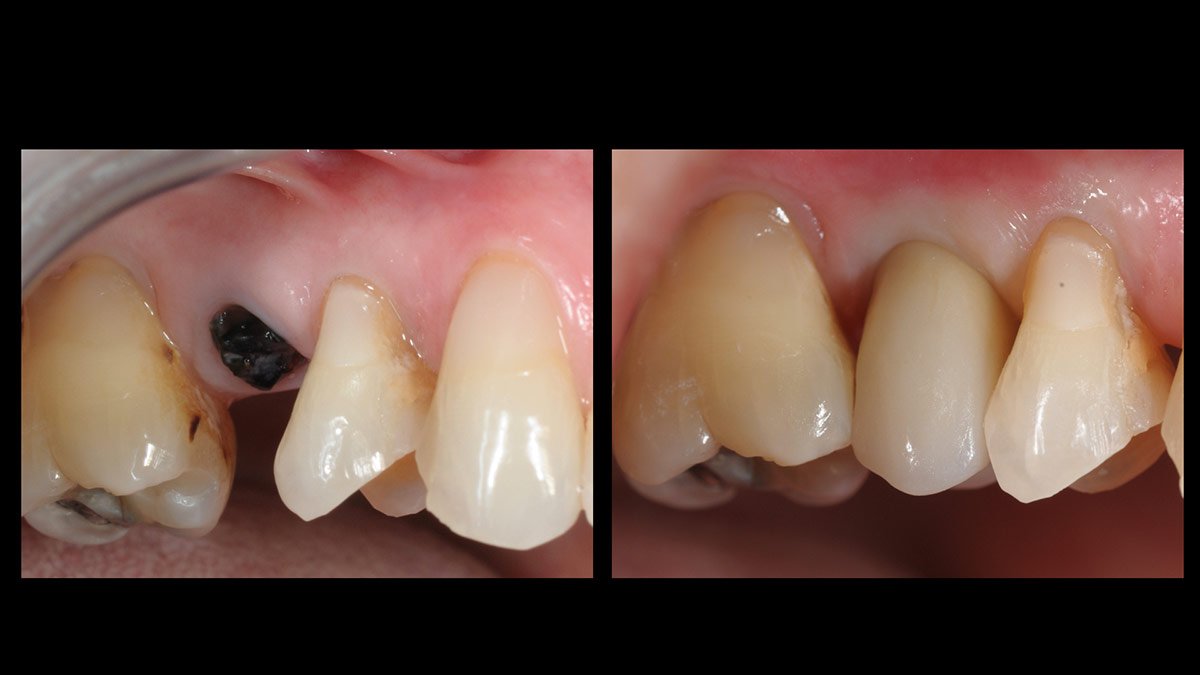

Immediate molars predictable? A case by @immediate_implantology